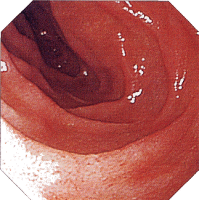

縦走潰瘍 敷石像 不整形潰瘍

クローン病画像 クローン病画像 クローン病画像

提供:牧山和也先生